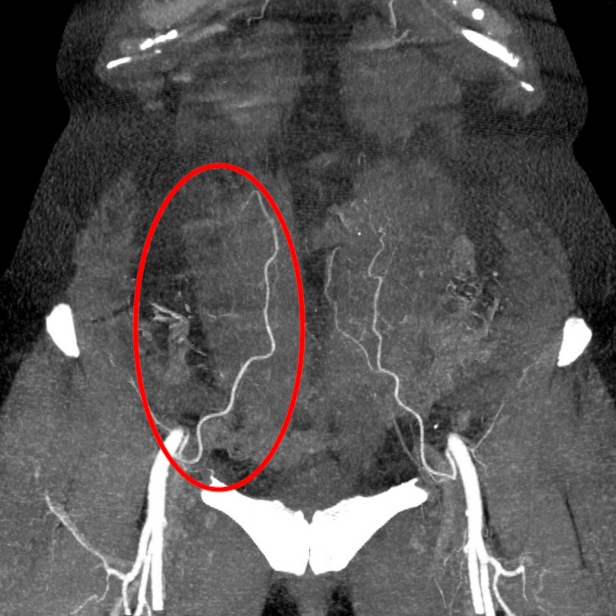

Patient presents with rectal mass. Pelvic MRI shows the mass invading the muscularis propria, with two suspicious mesorectal lymph nodes. Below is from the staging CT. What stage is her disease?

IIIA